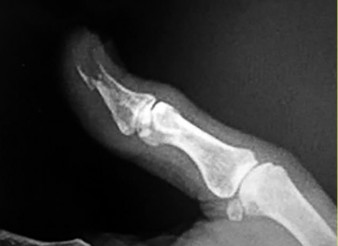

- المفاصل بين السلامية (PIP و DIP): تربط السلاميات ببعضها البعض داخل كل إصبع.

- الخلوع: خلع المفاصل، مثل خلع المفصل المشطي السلامي (MCP) أو المفصل بين السلامي القريب (PIP)، يمكن أن يؤدي إلى ألم شديد وفقدان الوظيفة.

القيود في الحركة (Limited Range of Motion):

- صعوبة في ثني أو مد المفصل بالكامل: شائع في حالات التهاب المفاصل، بعد الكسور، أو بسبب تقلصات الأنسجة (مثل تقلص دوبويتران).

- تشوه في وضعية الأصابع أو الرسغ: مثل تشوه الرقبة البجعية (Swan-neck deformity) أو تشوه الأزرار (Boutonniere deformity) في التهاب المفاصل الروماتويدي أو بعد إصابات الأوتار.